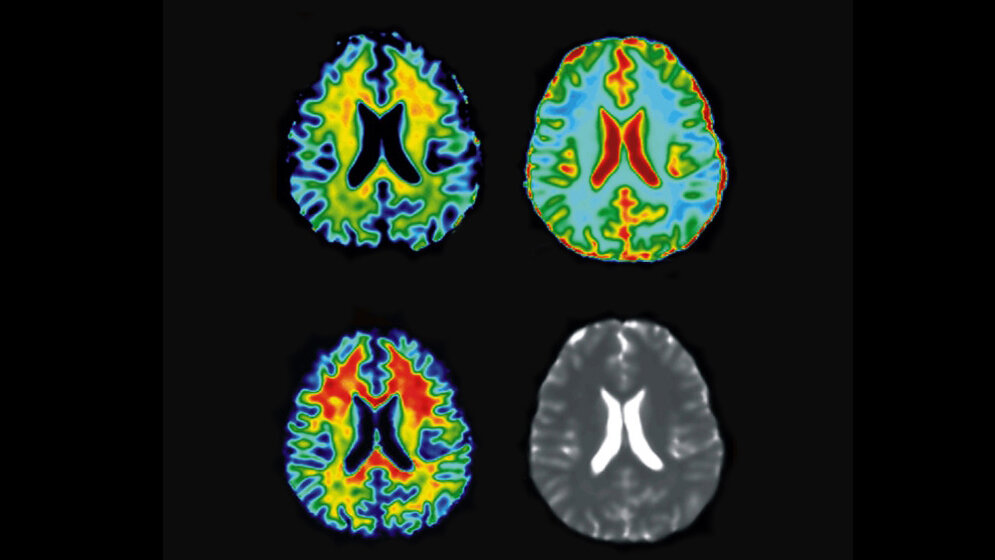

Die sogenannte CEST-Methode macht sich zu Nutze, dass Tumoren beim Wachsen große Mengen an Glukose benötigen. Die Forscher wollen die Verteilung der Zuckerverbindungen im Gehirn messen und dadurch die Krebszellen aufspüren - denn diese verbrauchen im Vergleich zu gesunden Zellen mehr Nährstoffe. Um die Glukose vor der Messung zu sich zu nehmen, müssten die Patienten lediglich Zuckerwasser trinken.

Üblicherweise wird bislang die sogenannte Positronen-Emissions-Tomographie (PET) verwendet, um tumoröses Gewebe zu identifizieren. Hier muss die Glukose allerdings radioaktiv markiert werden, was eine Belastung für die Patienten verursacht. Zudem steht in vielen Kliniken ein solcher PET-Scanner nicht zur Verfügung. Könnte man die Krebsfrüherkennung also auch mit einem MRT durchführen, wäre viel gewonnen: Diese Geräte sind in der Medizin viel weiter verbreitet und zudem kostengünstiger.

Die üblichen MRT-Geräte können aber bislang solch geringe Glukosekonzentrationen nicht darstellen. Die Wissenschaftler haben daher eine Technik entwickelt, durch die sie auch sehr niedrige Glukose-Konzentrationen mittels MRT messen können.